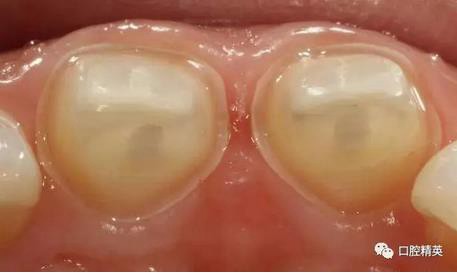

術前檢查

可見兩側(cè)齦緣外形不平整

齲洞低已近髓